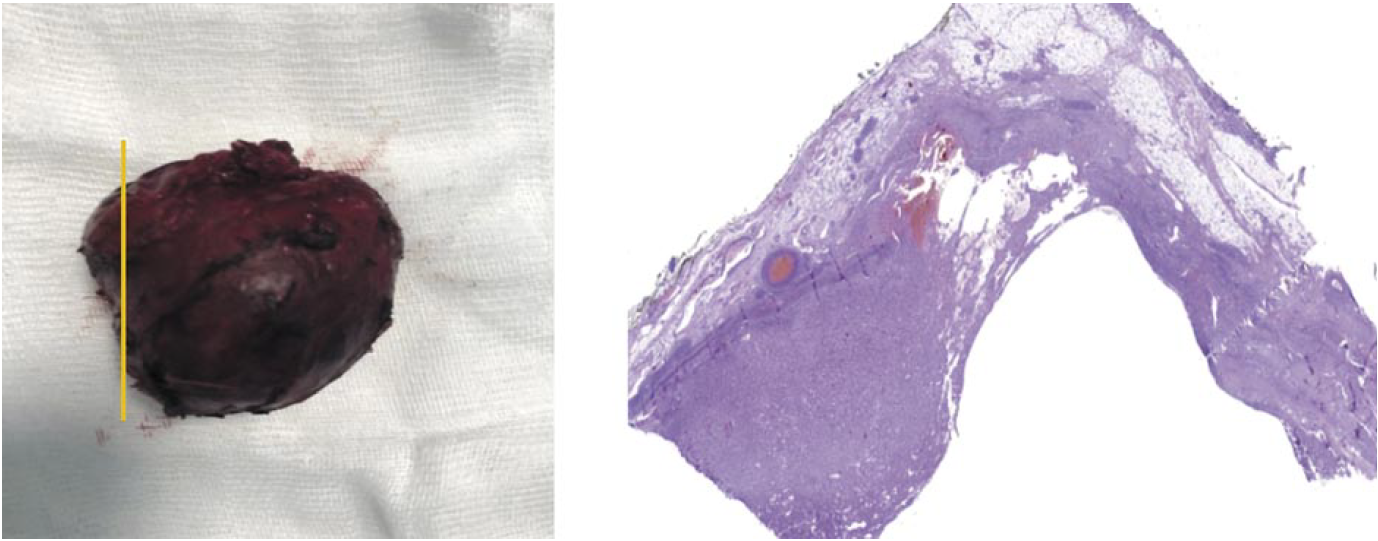

При макроскопическом исследовании опухоль представлена серым эластичным узлом размером 5,0×5,0×4,0 см. На разрезе опухоль кистозного вида с гладкой внутренней поверхностью и наличием тонкостенных перегородок. В просвете кистозных полостей содержится кровянистая жидкость. Толщина стенок кистозной опухоли на большем протяжении составляет 0,3–0,5 см с наличием участка утолщения до 1,0 см (рис. 8). К наружной поверхности опухолевого узла с одной из сторон плотно прилежит резецированный фрагмент мышечного слоя стенки пищевода размером 4,0×4,0 см.

Рис. 8. Рак паращитовидной железы. Общий вид кистозной опухоли с участком утолщения стенки кисты. Окраска гематоксилин-эозином, ×25.

Fig. 8. Parathyroid cancer. A general view of a cystic tumor with a section of thickened wall of the cyst. Hematoxyline-eosine staining, ×25.

При микроскопическом исследовании опухоль с крупными кистозными полостями. Стенки кист представлены опухолевой тканью, формирующей солидные, ацинарные и трабекулярные структуры из главных клеток (рис. 9). Опухолевые клетки мелкого и среднего размера с округлыми и овальными ядрами, светлой и слабоэозинофильной цитоплазмой. Ядерный полиморфизм выражен слабо с наличием мелких очагов опухолевых клеток с умеренно полиморфными ядрами. Фигуры митозов и очаги некрозов не визуализируются. Опухоль окружена фиброзной капсулой с наличием в области утолщения множественных участков грибовидной капсулярной инвазии и очагов инвазивного роста в прилежащую жировую клетчатку (рис. 10). Также обнаружены признаки сосудистой инвазии (рис. 11).

Рис. 9. Рак паращитовидной железы. Опухоль состоит из главных клеток, формирующих солидные, ацинарные и трабекулярные структуры. Окраска гематоксилин-эозином, ×100.

Fig. 9. Parathyroid cancer. The tumor consists of the main cells that forming solid, acinar and trabecular structures. Hematoxyline-eosine staining, ×100.

Рис. 10. Рак паращитовидной железы. Экстракапсулярная инвазия опухоли в прилежащую клетчатку. Окраска гематоксилин-эозином, ×50.

Fig. 10. Parathyroid cancer. Extracapsular tumor invasion into the adjacent fibers. Hematoxyline-eosine staining, ×50.